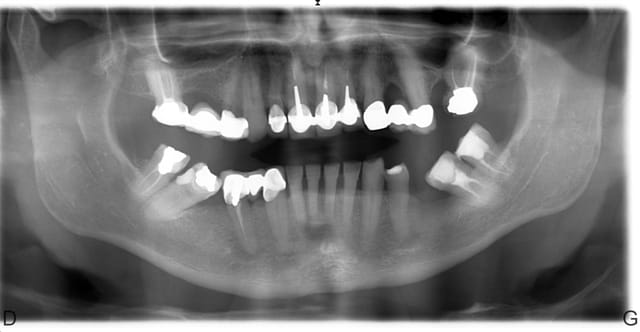

voici la pano de mon patient

motif consult : "des trucs qui s’ébrèchent à droite et à gauche et bourrages en bas à D "

qu'en pensez vous ? les 47-48-37-38 versées me chagrinent mais pas le temps de redresser car contrainte : patient part début juillet , ca doit etre fini ;

-la pano ne donne pas l'état paro de 37 47: sondage?

le patient bruxe (facettes d'usure visibles)

1) simulation sur les modèles des extractions de 47 48 37 38 28, faire réaliser un PPA immédiate qui respecte les courbes d'occlusion (tailler les faces occlusales des dents antagonistes sur le modèle maxillaire avant)

2) Extraction de 47 48 37 38 28 , pose d'un PPA immédiate qui respecte les courbes d'occlusion et démonter les bridges qui ne respectent pas les courbes d'occlusion